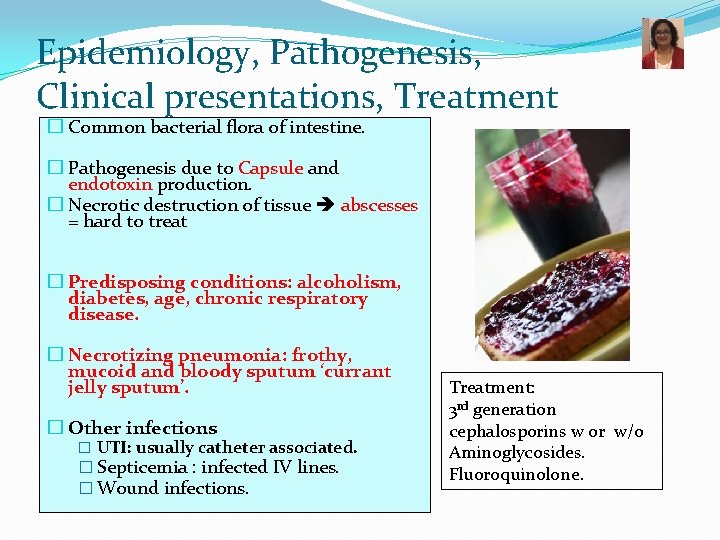

Epidemiology, Pathogenesis, Clinical presentations, Treatment � Common bacterial flora of intestine. � Pathogenesis due to Capsule and endotoxin production. � Necrotic destruction of tissue abscesses = hard to treat � Predisposing conditions: alcoholism, diabetes, age, chronic respiratory disease. � Necrotizing pneumonia: frothy, mucoid and bloody sputum ‘currant jelly sputum’. � Other infections � UTI: usually catheter associated. � Septicemia : infected IV lines. � Wound infections. Treatment: 3 rd generation cephalosporins w or w/o Aminoglycosides. Fluoroquinolone.